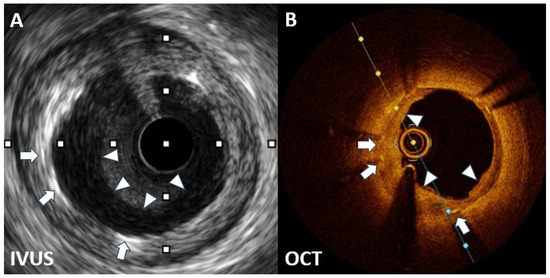

The Best Strategy for the Black Hole Phenomenon between Intravascular Ultrasound and Optical Coherence Tomography

- Castagna, M.T.; Mintz, G.S.; Weissman, N.; Maehara, A.; Finet, G.; Waksman, R. "Black hole": Echolucent restenotic tissue after brachytherapy. Circulation 2001, 103, 778. [Google Scholar] [CrossRef] [PubMed]

- Hirose, M.; Kobayashi, Y.; Leon, M.B. Echolucent neointimal hyperplasia "dark wall" after sirolimus eluting stent implantation. Heart 2004, 90, 1143. [Google Scholar] [CrossRef] [PubMed]

- Goto, K.; Shiode, N.; Shirota, K.; Fukuda, Y.; Kitamura, F.; Tominaga, K.; Kato, Y.; Miura, H.; Inoue, K.; Nobuyoshi, M. Pathological finding of sirolimus-eluting stent (SES) restenosis lesion with black hole appearance on intravascular ultrasound. Circ. J. 2009, 73, 1969–1971. [Google Scholar] [CrossRef] [PubMed]

- Otsuka, Y.; Murata, T.; Kono, M.; Imoto, H.; Koyama, T.; Nakamura, K.; Kadama, S.; Noguchi, H.; Saito, T. Black hole restenosis after drug-eluting stent implantation for in-stent restenosis: Potential mechanism and optimal strategy. Heart Vessels 2015, 30, 682–686. [Google Scholar] [CrossRef] [PubMed]

- Kurita, T.; Terashima, M.; Suzuki, T. Serial optical coherence tomography imaging of the “black-hole” phenomenon by intravascular ultrasound following sirolimus-eluting stent implantation. EuroIntervention 2012, 7, 1480–1481. [Google Scholar] [CrossRef] [PubMed]

- Landmesser, U. Optical coherence tomography (OCT) evaluation after coronary stenting: The "black hole" and other low OCT signal-intensity areas. EuroIntervention 2012, 7, 1367–1371. [Google Scholar] [CrossRef] [PubMed][Green Version]